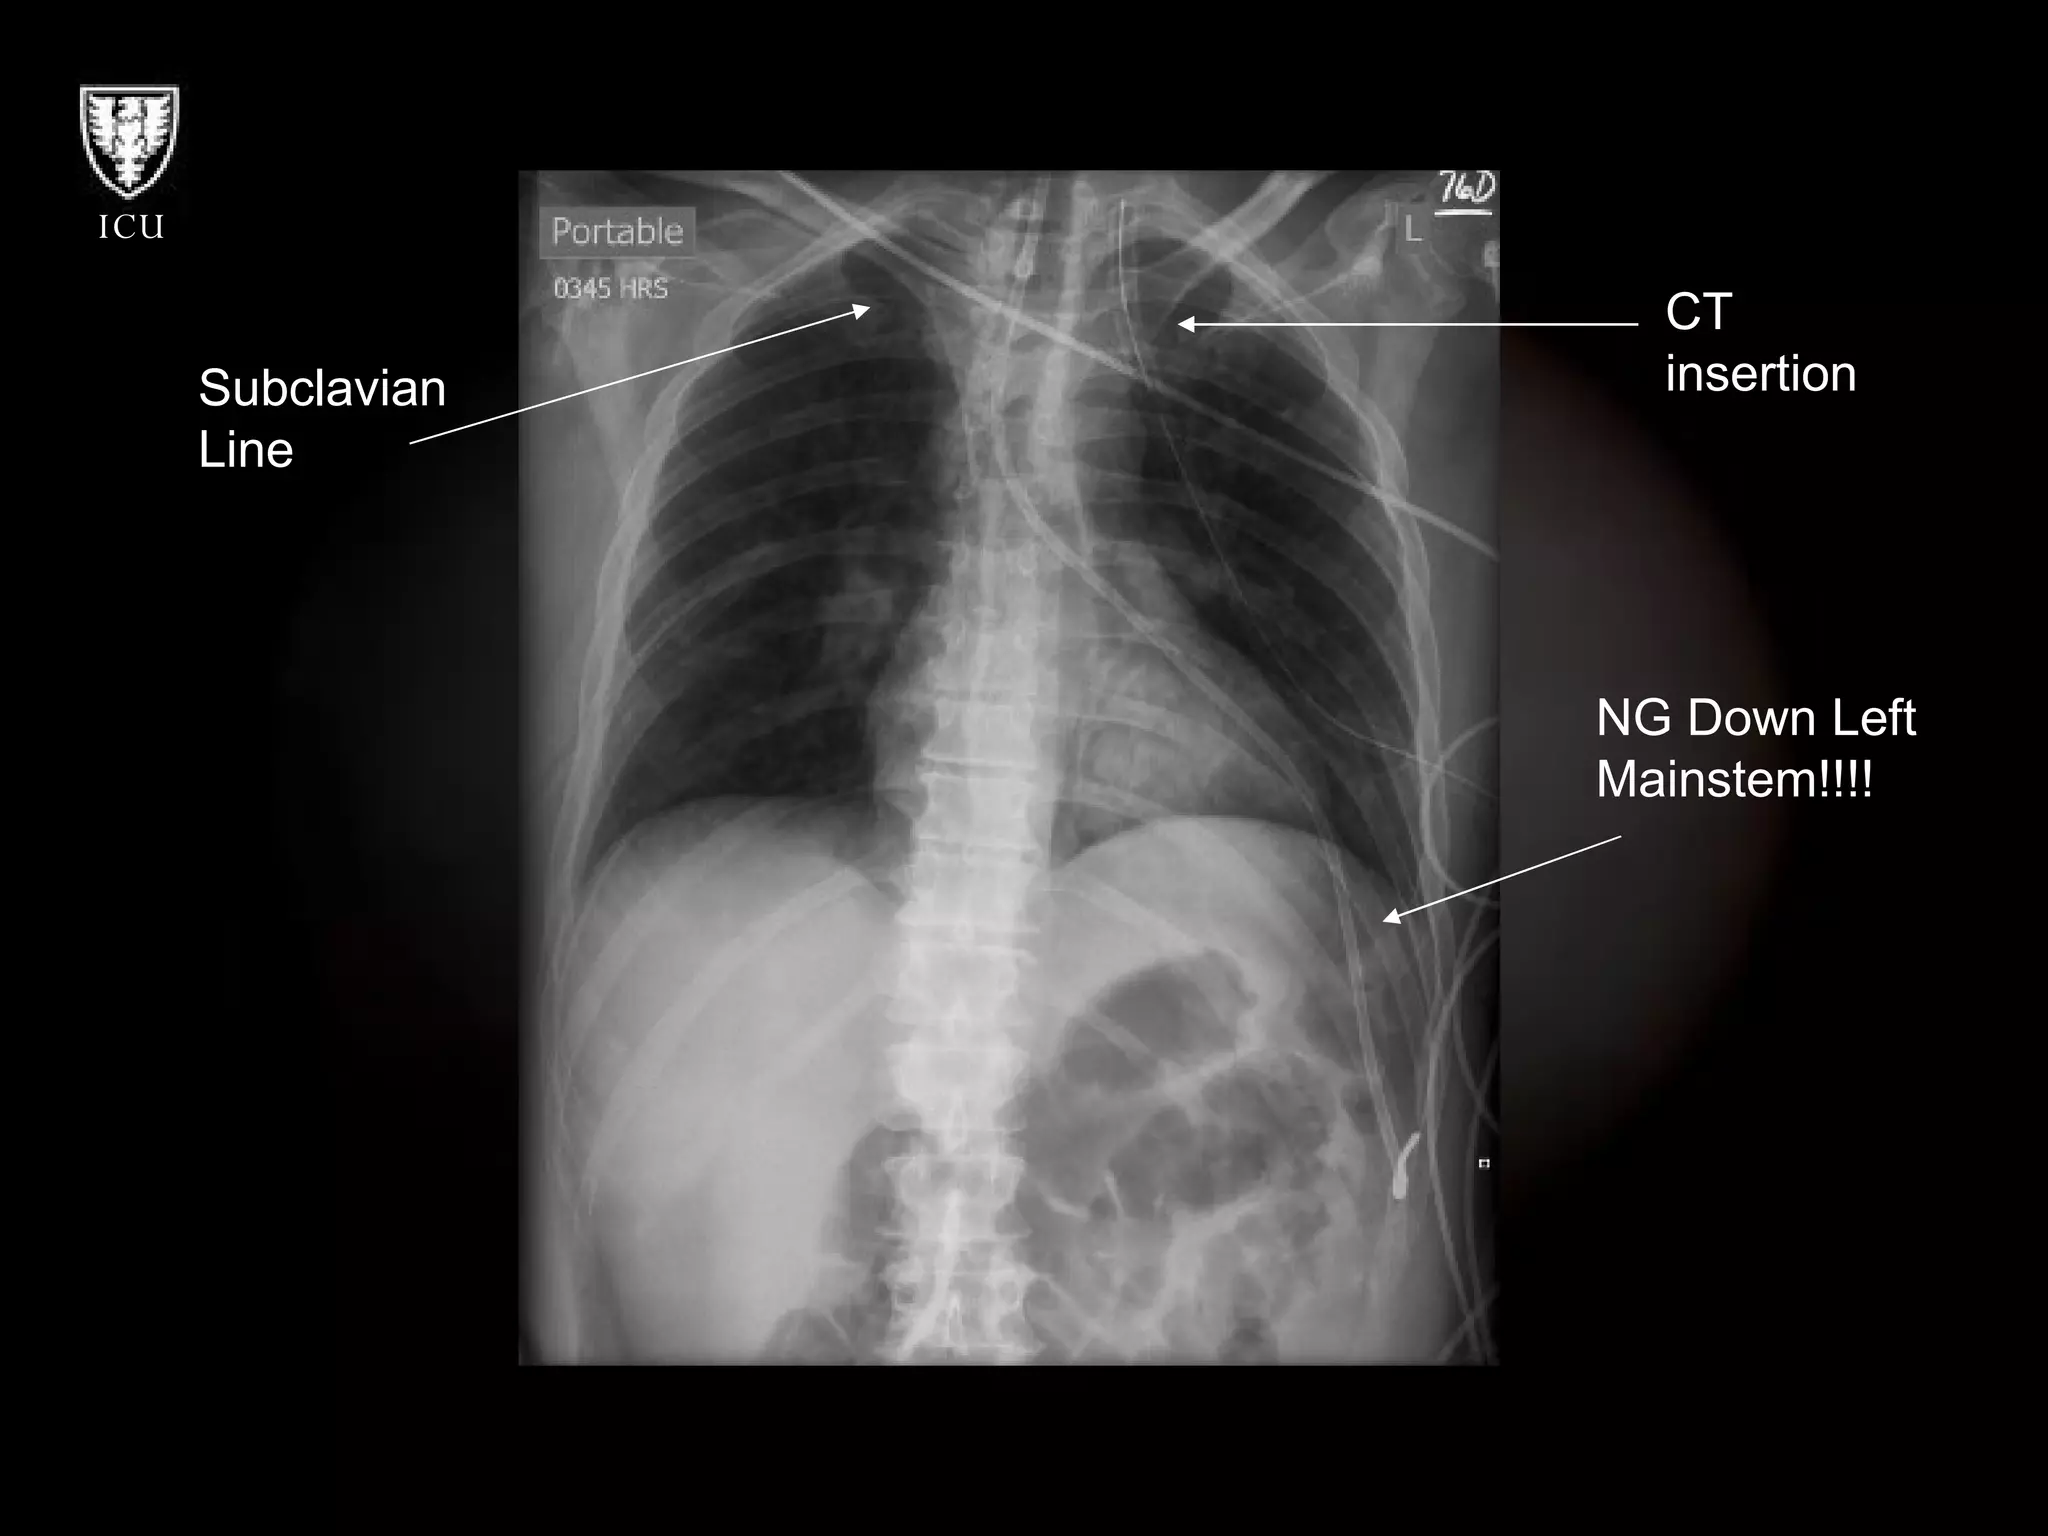

What’s Wrong With These Pictures?

CT insertion Subclavian  Line NG Down Left Mainstem!!!!

What’s Wrong WithThese Pictures?